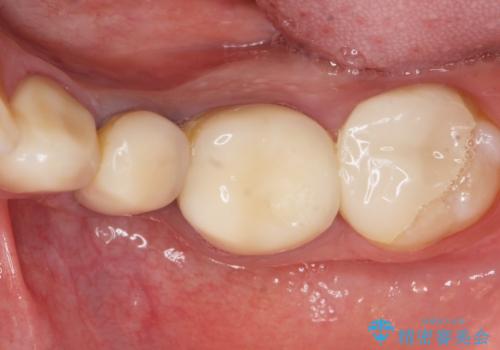

セラミッククラウンの天然歯のような自然な仕上がりと咬み心地に喜んで頂けました。

クラウンの種類:オールセラミッククラウン スタンダード